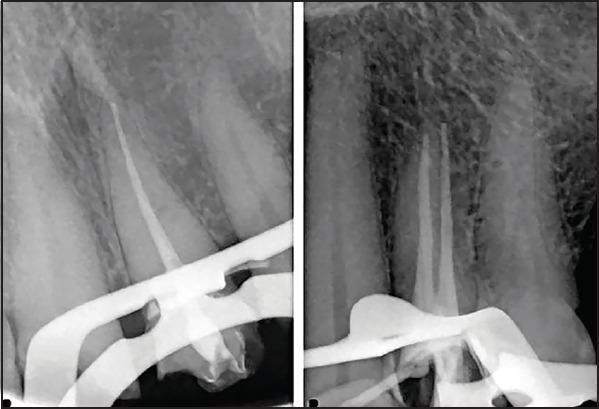

To evaluate the radiographic technical quality of root canal fillings performed by senior dental students at Alfarabi colleges for dentistry, Kingdom of Saudi Arabia.

Radiographic assessment was conducted for 246 teeth (390 root canals) endodontically treated by senior dental students to evaluate the quality of root canal fillings. Three criteria were evaluated to assess the technical quality of root canal fillings: length, density, and taper. The root canal filling was considered acceptable if it had an adequate length with no voids and consistent taper from the orifice to the apex. Statistical analysis was conducted using Kruskal-Wallis, Mann-Whitney, and chi-square tests (P=0.05).

Acceptable root canal fillings were detected in 127 (32.6%) patients. The frequency of an acceptable root canal filling was the highest for the upper anterior teeth (40%). There were significant differences in the length and density among the types of teeth (P<0.05). However, there was no significant difference in the taper among the types of teeth (P>0.05).

The quality of root canal fillings performed by senior undergraduate dental students at AlFarabi colleges for dentistry was acceptable in 32.6% of patients. This outcome enhanced the poor performance of undergraduate dental students in the area of endodontics.